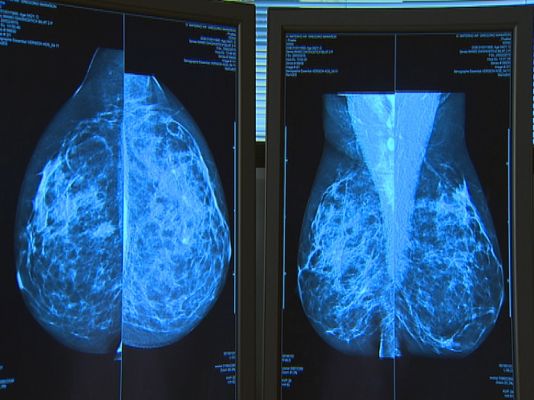

Andalucía se tiñe hoy de rosa por el Día del Cáncer de Mama. Como esta mesa en Córdoba, hay desplegados múltiples puntos de información en toda la comunidad. Este año 23.000 andaluzas son o van a ser pacientes de esta enfermedad. En más del 80% de los casos, el cáncer de mama se cura.

Unas seis mil mujeres andaluzas van a ser diagnosticadas de cáncer de mama este año. Hoy, en el Día Internacional, hablamos con una mujer que ha sobrevivido a este tipo de cáncer. La prevención y los nuevos tratamientos, ahora menos invasivos, están ayudando a la recuperación.